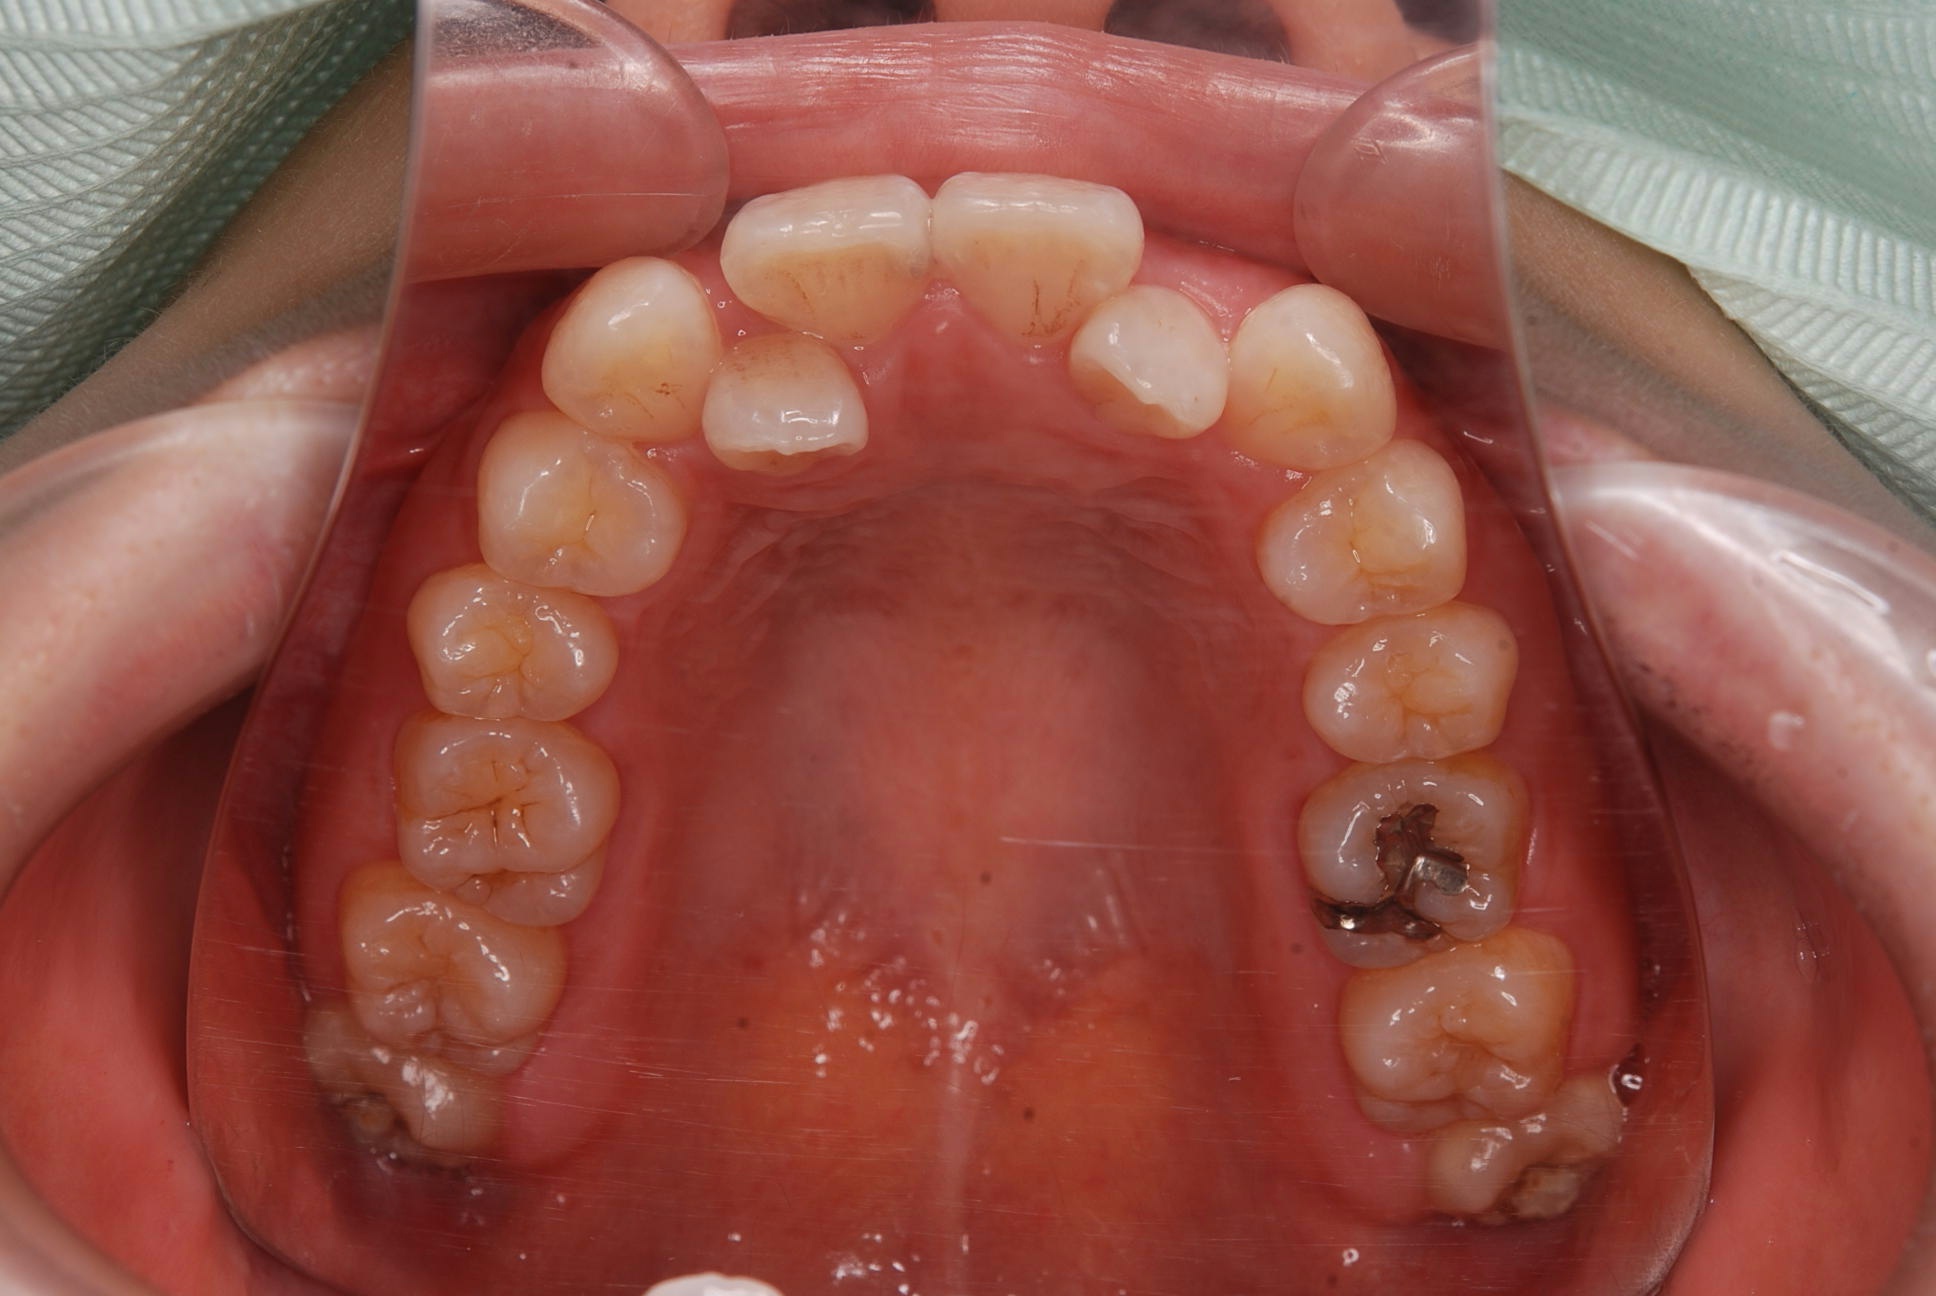

上下顎に叢生(歯並びのガタガタ) と部分的な反対咬合を認める。

本症例は上下小臼歯抜歯により叢生解消のスペースを獲得し、下顎位の後退があることからダイレクトスプリント治療を併用して顎位の安定を求めた。

矯正用アンカースクリューは固定源の強化のために必要とした。